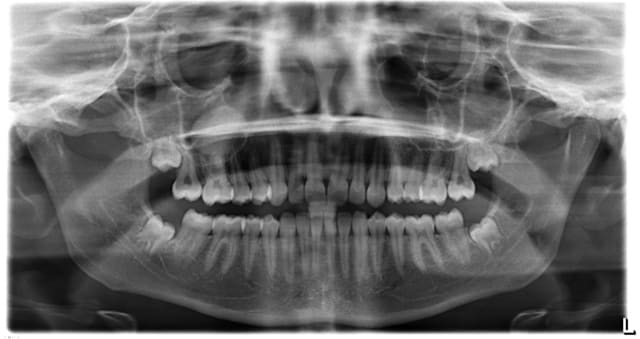

Jeune patiente de 18 ans qui vient pour un contrôle de ses dents de sagesse, je fais une pano et je remarque une image radio au niveau du sinus droit, la patiente ne ressent rien, c'est asymptomatique, a votre avis quel est votre diagnostic

Voilà une image similaire dans le sinus gauche.

J'avais adressé à l'ORL qui avait fait faire un scanner des sinus et diagnostiqué un polype.

Ceci étant totalement asymptomatique, il a décidé de ne rien faire.

Je revois mon patient régulièrement pour contrôler l'implant et à chaque fois la lésion ne montre aucune évolution.